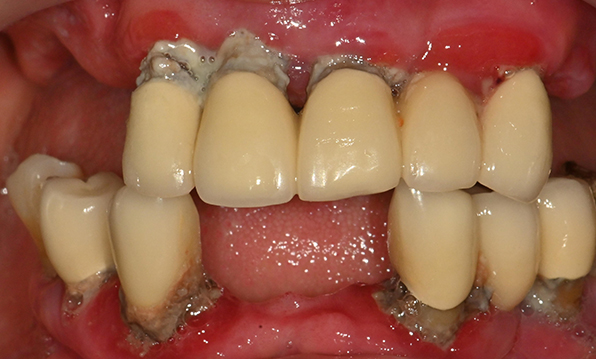

Before & After

| Before | After |